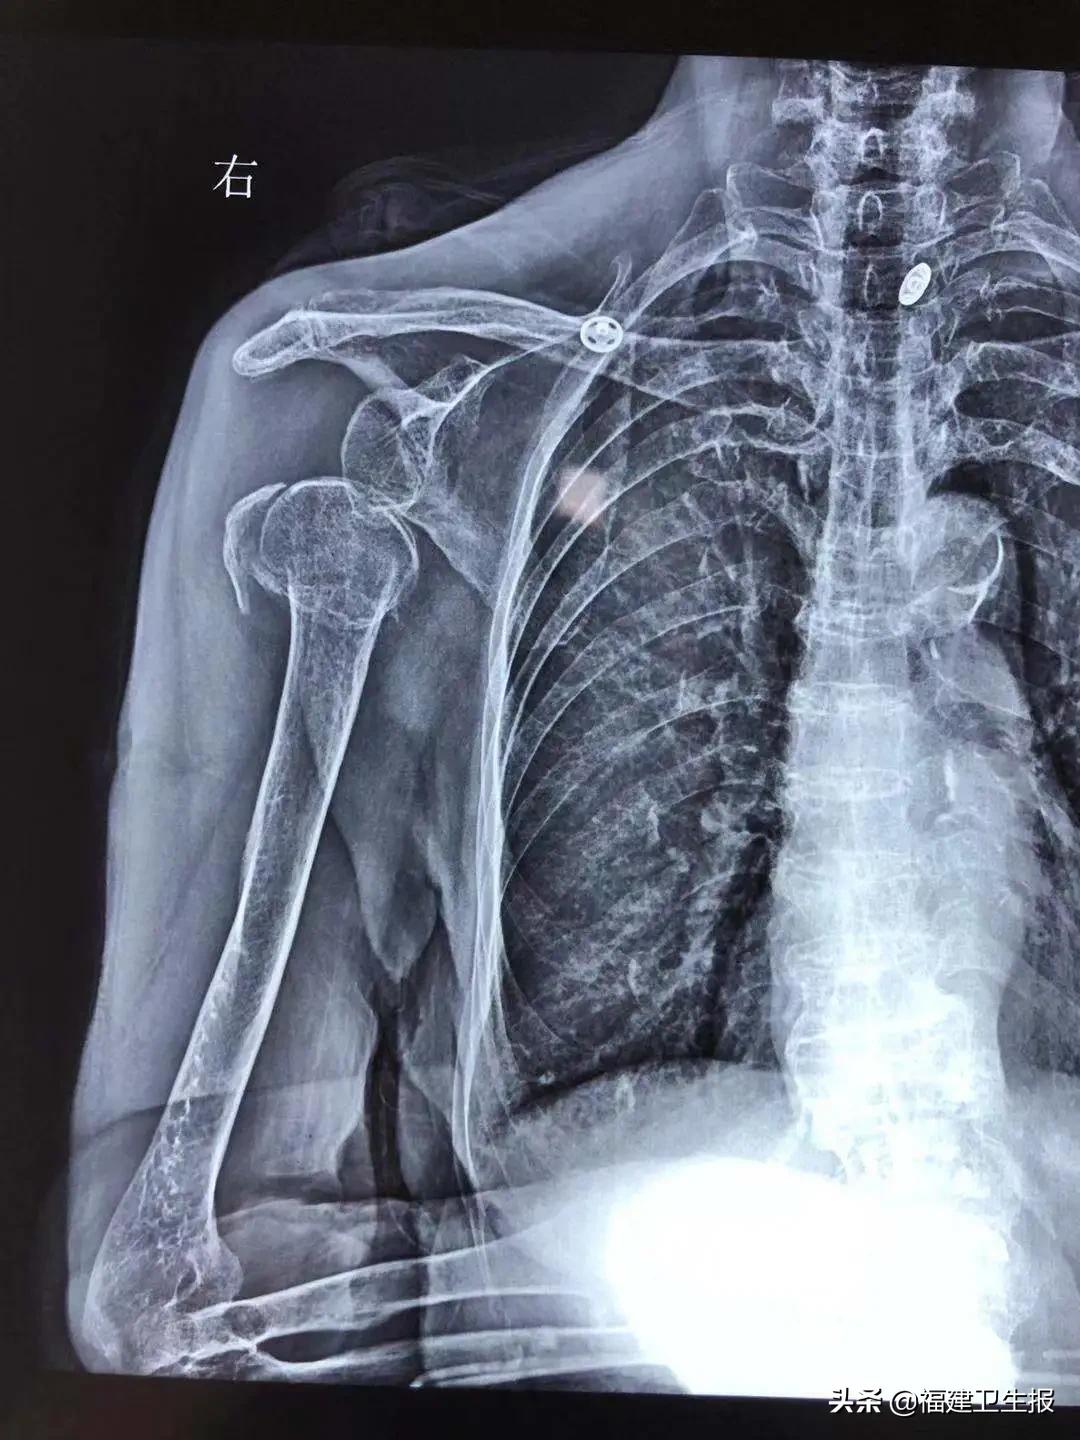

经过拍片检查,运动医学科主任李坚诊断黄奶奶为“右肩关节再次脱臼伴肱骨近端粉碎性骨折”,建议她做肩关节人工肱骨头置换术。

术前